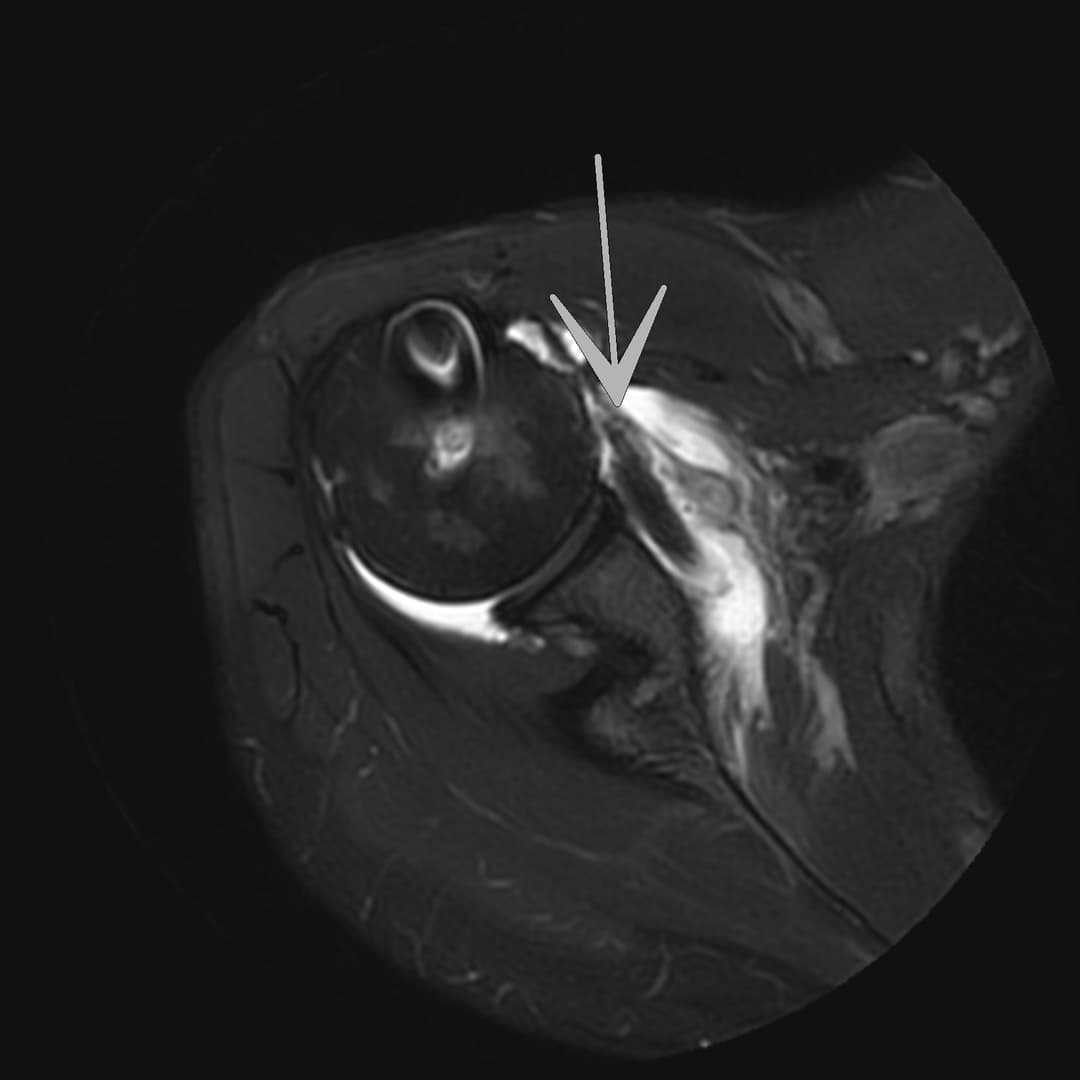

IRM

Ténodèse du long biceps intacte. Tendons sus et sous épineux respectés. Large diffusion du contraste depuis compartiment articulaire vers la BSAD.

Rupture du tendon sous-scapulaire avec rétraction grade II-III